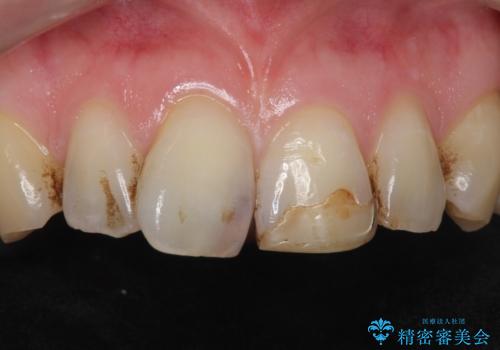

- 前歯のプラスチックの詰め物が気になると来院された患者様です。

左上の前歯に詰められたプラスチック(コンポジットレジン)は、劣化し変色していました。

レジンを除去したところ二次う蝕を認めたため、丁寧に虫歯をとりました。